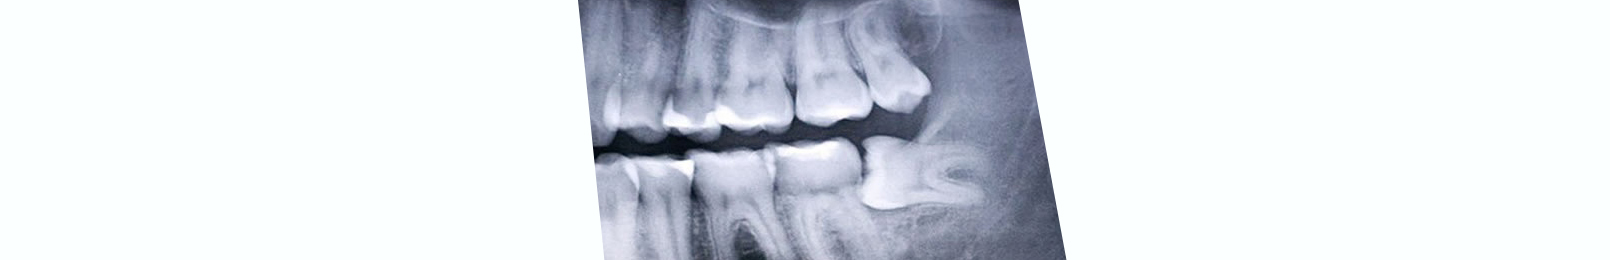

Many people who have one or more missing teeth are candidates for a dental bridge. The teeth that will support the bridge must be in good health and have good bone support. But the difference between correct and incorrect oral hygiene is an important factor in the success of the dental bridge.

There are several different types of dental bridges. Your dentist or oral health specialist will recommend the one that's best for your mouth condition and the location of the missing tooth or teeth.

• Traditional bridge. As described above, this bridge is made up of a false tooth held together by two crowns. The three pieces are then cemented to the surrounding teeth on each side of the gap.

• Resin-bonded bridge or Maryland bridge. The false teeth are bonded to the back of the teeth on both sides of the gap with metal or porcelain wings to span the gap. This procedure is common when the teeth missing are in the front of the mouth. This is a conservative approach. But it has a higher failure rate than traditional bridges.

• Cantilever bridge. This type of procedure is appropriate only when there is only one tooth to act as support for the tooth being replaced. It's not as strong as a traditional bridge since it's only supported by a natural tooth on one side. This one-sided support sets up a "lever" effect. This can weaken the supporting tooth over time. This type of bridge will have a higher success rate when placed with the false tooth in a more front position in the mouth than the supporting tooth. It's also advisable to have cantilever-type bridges in the front of the mouth, rather than the back. That is because biting compression forces are greater in the back of the mouth.